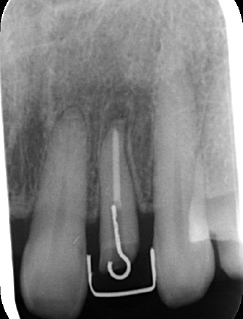

左上2は広範囲にわたってCRが充填されているのがわかります。またその周囲に透過像があり、カリエスになっていることもわかります。

| 根の中の薬が十分に充填されておらず、根の先が周りと比べて黒くなっており、炎症があると判断できます。 | 根の中にしっかりとお薬を緊密に充填しましたが、まだ根の先に黒くなっている部分があります。 |